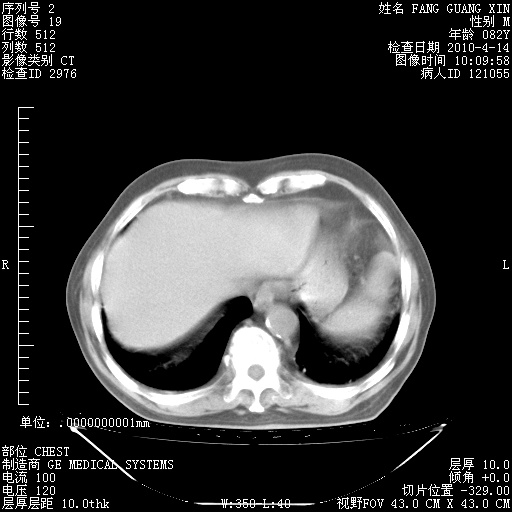

4月14日肺部CT

23.JPG

24.JPG

25.JPG

26.JPG

肺部CT平扫未见异常。